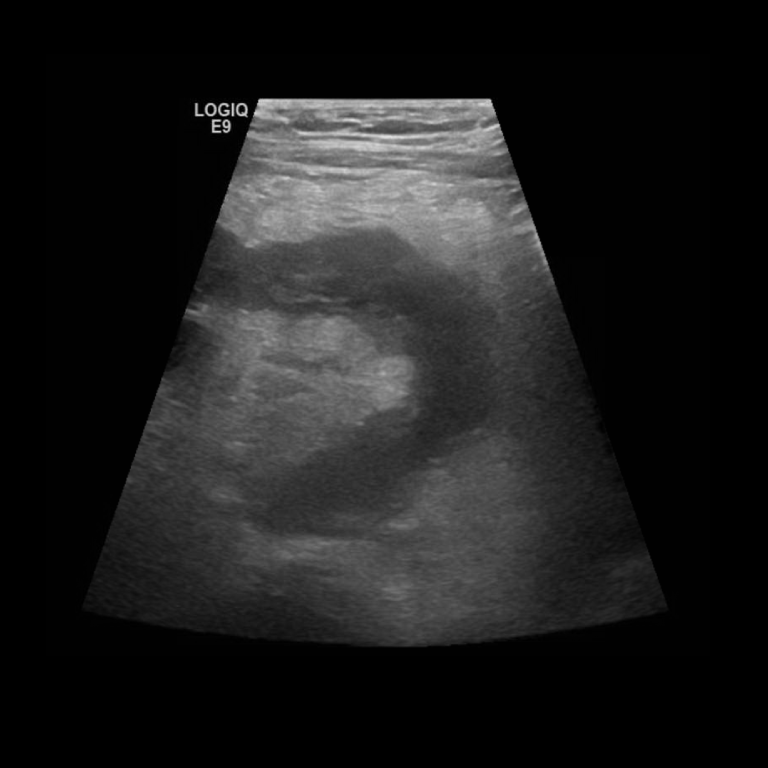

US image showing a transverse section of a normal appendix twice due to ...

The abdominal US evidences a thickened appendix with circular ...

There is marked thickening of parts of the appendix up to a diameter of ...

Longitudinal view of a thickened, oedematous appendix measuring 10 mm ...

US image shows the longitudinal section of a normal appendix. The ...